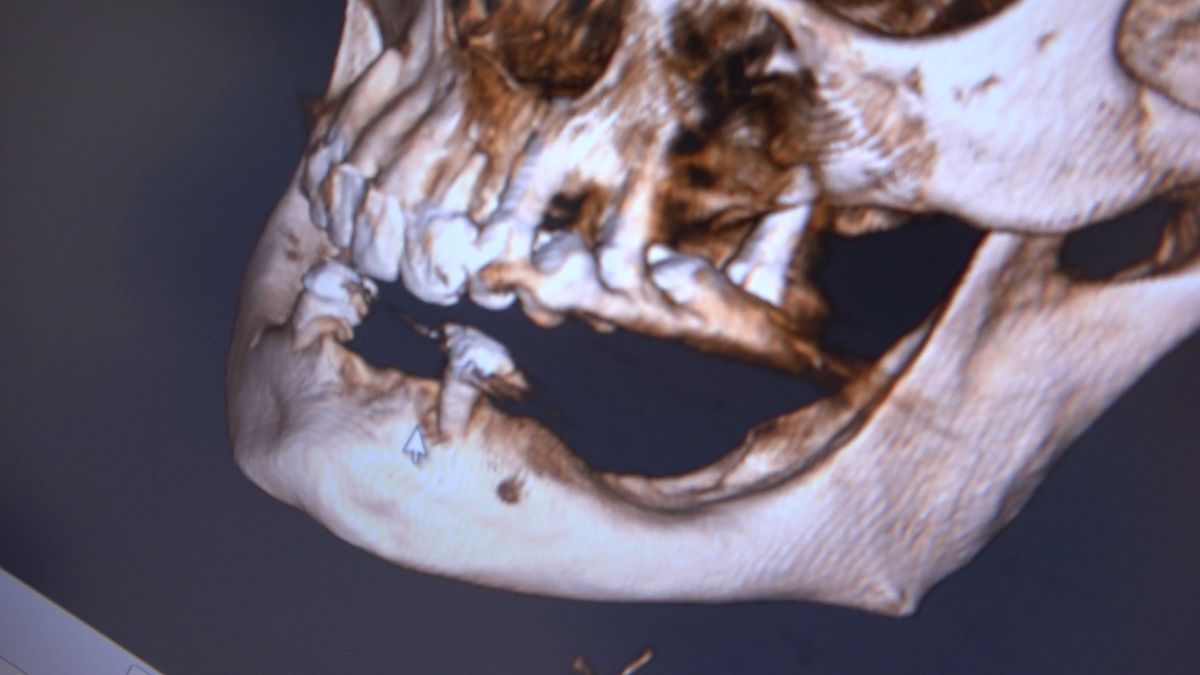

Practiculum Implantologii – Sezon VIIB, sesja 7, dzień 2